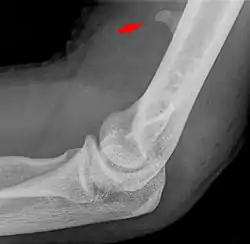

Small supracondylar process seen on a lateral radiograph of the elbow

The supracondylar process of the humerus (also known as an avian spur) is a variant bony projection on the anteromedial aspect of the upper arm bone (humerus), about 5–6 cm above the medial epicondyle.[1] It is directed downward, forward and medially pointing to the medial epicondyle. A fibrous band, Struthers ligament, may connect this process to the medial epicondyle.[2] This variation has a prevalence of 0.68% and is significantly more common in women than in men.[3]